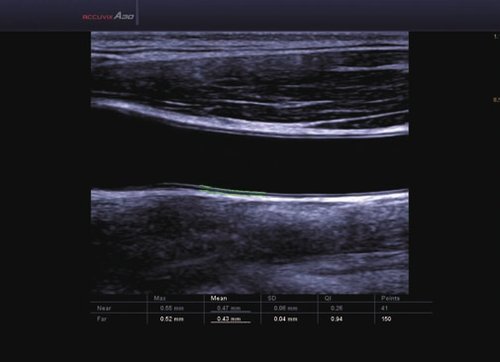

1 L4-7 Linear 4-7 MSK, Gefäße, Tiefe Venen

2 L5-13IS Linear 6-12 MSK, Weichteile, Gefäße, Brust

3 L5-13/50mm Linear 5-13 MSK, Weichteile, Gefäße

4 LS6-15 Linear 6-15 MSK, Weichteile, Gefäße

5 L7-16IS Linear 7-16 MSK, Weichteile, Gefäße, weibliche Brust, Pädiatrie, Oberfläche

• ElastoScan™ ermöglicht eine genauere Visualisierung von Tumoren und erfasst und dokumentiert Gewebesteifheiten.